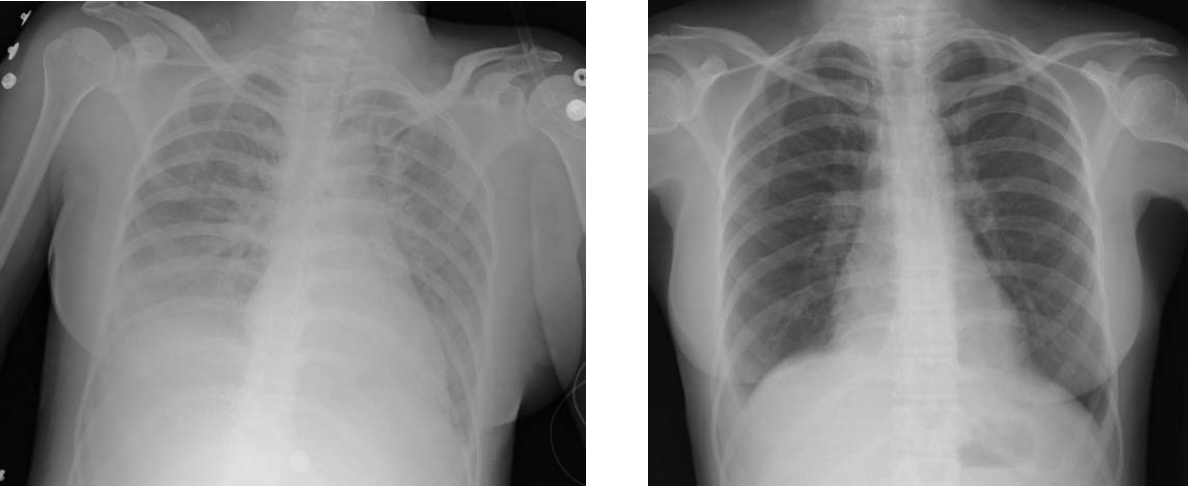

임상적으로는 빈호흡과 함께 1회 환기량 감소가 관찰된다. 산소 포화도와 동맥혈 산소 분압(PaO2)은 급격히 감소한다.[60] 북미 및 유럽 컨센서스 회의(NAECC)에서는 P/F 비율(동맥혈 산소 분압(PaO2, mmHg)을 흡입 공기 중 산소 분율(FiO2)로 나눈 값)이 200 이하일 경우 ARDS로 정의했다.[60] 참고로 P/F 비율이 300 이하인 경우는 급성 폐 손상(ALI)으로 정의하며, ALI 환자의 약 4분의 1은 7일 이내에 ARDS로 진행될 수 있다.[60] 그 외에 수치로 나타내야 할 명확한 진단 기준은 아직 정해지지 않았다.[61] 흉부 X선 검사에서는 폐에 현저한 침윤 소견이 보인다.

- '''영상 소견''': 흉부 X선이나 CT 스캔에서 양쪽 폐에 불투명 음영(불투과성)이 나타나며, 이는 흉막 삼출액, 폐엽/폐허탈, 또는 결절 등으로 설명되지 않아야 한다.

의료 영상 검사는 오랫동안 ARDS 진단의 중요한 기준이었다. 초기에는 흉부 X-선 소견이 필수였으나, 현재는 CT나 초음파 소견도 진단에 활용된다. 일반적으로 심부전과 같은 심장 혈관 압력 증가와 관련이 없는, 양쪽 폐에 영향을 미치는 체액 축적(폐부종)의 방사선 소견이 ARDS를 시사할 수 있다.[18]

임상적으로는 산소 포화도와 동맥혈 산소 분압이 급격히 감소한다. 또한 빈호흡(호흡 빨라짐)과 1회 환기량 감소가 나타날 수 있다. 흉부 X선 사진에서는 양쪽 폐에 현저한 침윤(허옇게 보이는 부분)이 관찰된다.